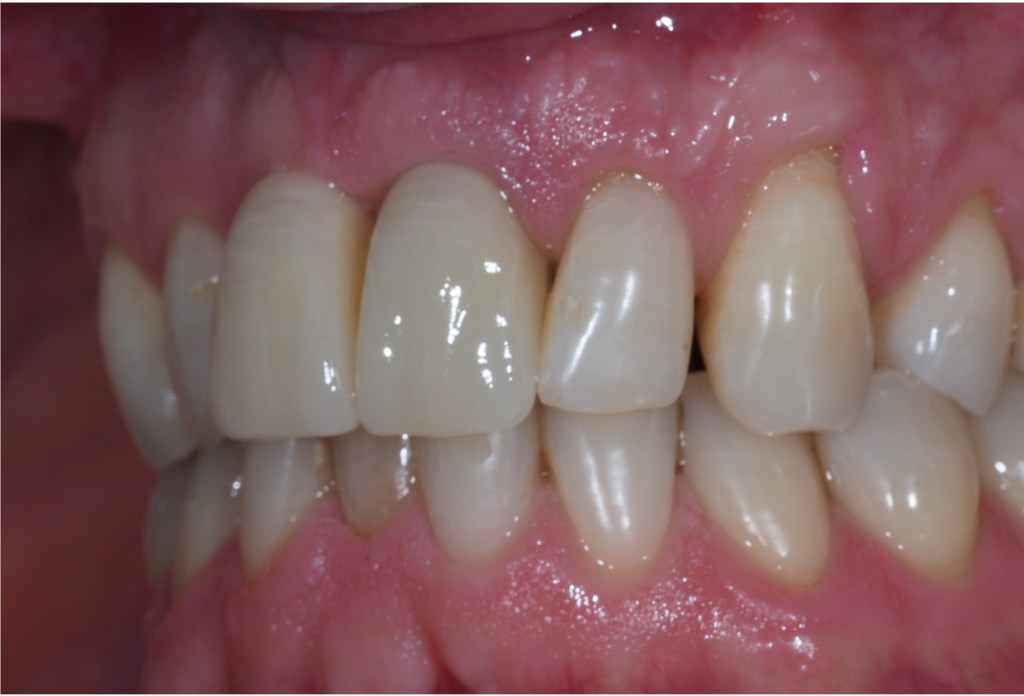

Two missing teeth can be replaced by a single dental implant. This is often the case if there is not enough bone at both sites or the space is too narrow for two implants. It can also reduce the cost of treatment. As long as the bite forces are controlled and a strong implant is used these can be a very successful treatment.